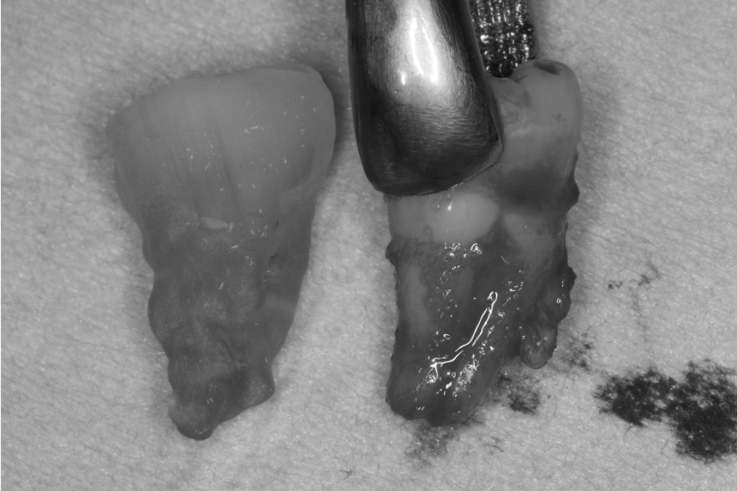

術前に撮影したCT画像から3Dプリンターを用いて親知らずのレプリカを作製することで、 親知らずが乾燥することを防ぎ、成功率が上がるよう努力しています。 |

抜歯が必要になった際に余っている親知らずがあれば移植歯として利用することができます。 術前に撮影したCT画像から3Dプリンターを用いて親知らずのレプリカを作製することで、親知らずが乾燥することを防ぎ、成功率が上がるよう努力しています。 |